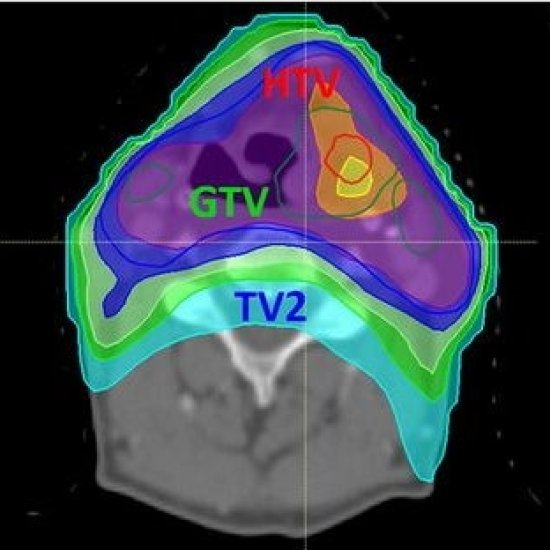

News • Two tracers, one target

Beyond "one-size-fits-all": A new strategy that combines two types of PET scans can guide personalized radiotherapy for head and neck cancers, according to new research. |